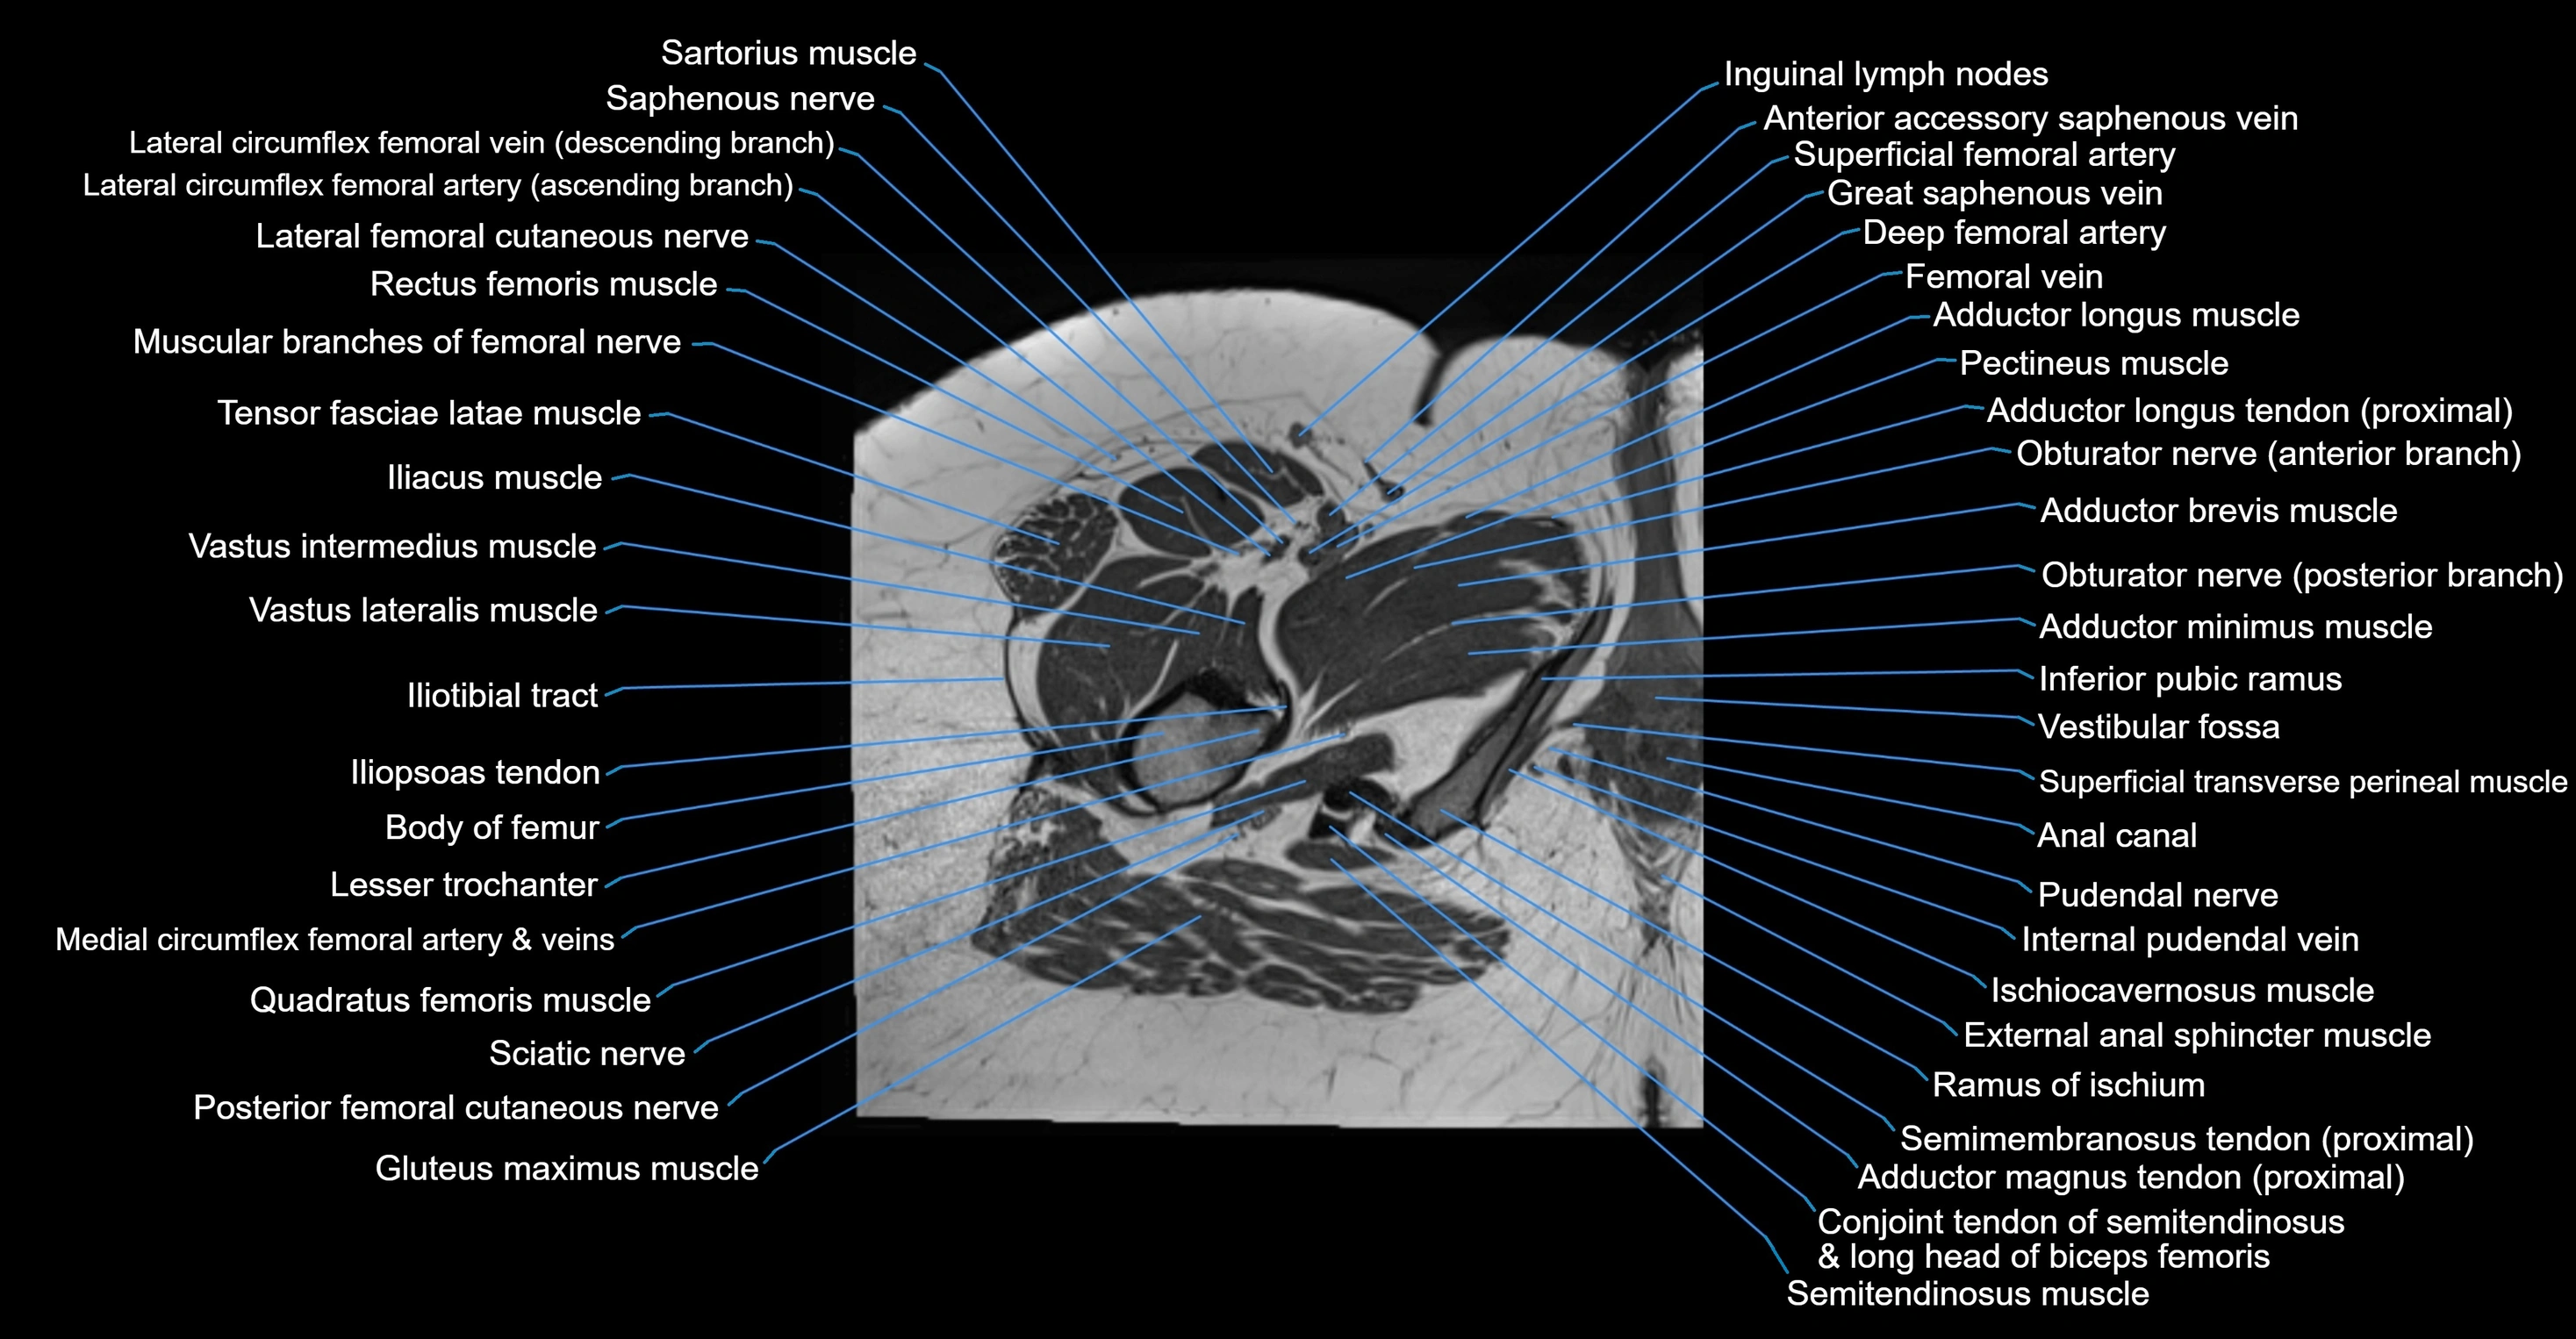

- Adductor brevis muscle

- Adductor longus muscle

- Adductor magnus muscle

- Adductor minimus muscle

- Anal canal

- Conjoint tendon of biceps femoris & semitendinosus

- External anal sphincter

- Inferior pubic ramus

- Inguinal lymph nodes

- Ischiocavernosus muscle (Female)

- Lesser trochanter

- Posterior femoral cutaneous nerve

- Pudendal nerve

- Quadratus femoris muscle

- Rectus femoris muscle

- Sartorius muscle

- Semimembranosus tendon (proximal)

- Superficial transverse perineal muscle

- Tensor fasciae latae muscle

- Vastus intermedius muscle

- Vastus lateralis muscle

- Vestibular fossa